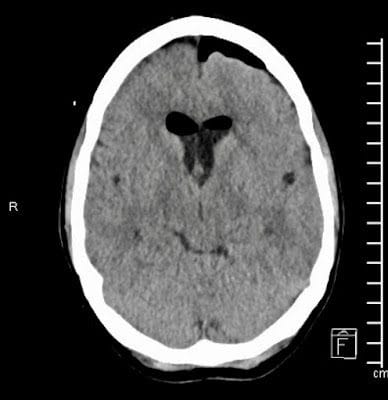

The Neuro surgeon, Dr. Christian Ramsey (who is such a great guy!), came in early Sunday morning and explained that the CT scan showed I had a Colloid Cyst (white dot in the above picture) in the third ventricle of my brain which was blocking the Cerebral Spinal fluid (CSF) from circulating causing Obstructive Hydrocephalus, which, if left untreated, could lead to death. He then explained that the best way to remove my cyst was the most risky and invasive way by making an incision in the top of my head (Craniotomy) and digging down through the Corpus Callosum, which separates both hemispheres of the Cerebrum, to reach the ventricles. Dr. Ramsey was pretty sure that my cyst was more solid, and therefore could not be performed endoscopically. He also explained that I was moved to the N-ICU (Neurology ICU) where I could be monitored pre and post-operative every hour due to my hydrocephalus and increased seizure risk, both of which were also being treated with IV medications. Even though Colloid Cyst are rare, Dr. Ramsey assured us that he was the right person for the job due to the fact he did a fellowship in Finland with the top Colloid Cyst specialist in the world, and he even wrote a paper on Colloid Cysts (tender mercy)! He ended up talking with us for a good forty-five minuets, but we still felt like we should get a second opinion or something, after all, this was brain surgery. So Brad had a long talk with our family physician, whom we really like and trust, and felt better about the whole thing, especially after finding out the two were good friends, and that Dr. Ramsey had already spoken with our family physician. Brad also asked our nurses what they thought of Dr. Ramsey and they all agreed that he was a very smart, dedicated and thorough doctor who really cared for his patients.

The surgery was a success, and the above picture is of my CT scan the afternoon after surgery. The cyst is gone and there is good flow of CSF through the ventricles. They also closed my skull with titanium plates and screws which the doctor assured me would not go off at the airport.

The beginning of this week I had another CT scan and met with Dr. Ramsey who was super happy with my progress and gave me the green light to drive, exercise, and start working again as long as I slowly ease back into things. I'm not allowed to swim yet, and I'll have my vision re-checked in a year or so due to some swelling of in the Optic Chiasm. I still battle with my memory and get headaches and some dizziness & nausea which is usually remedied by laying down a little each day.